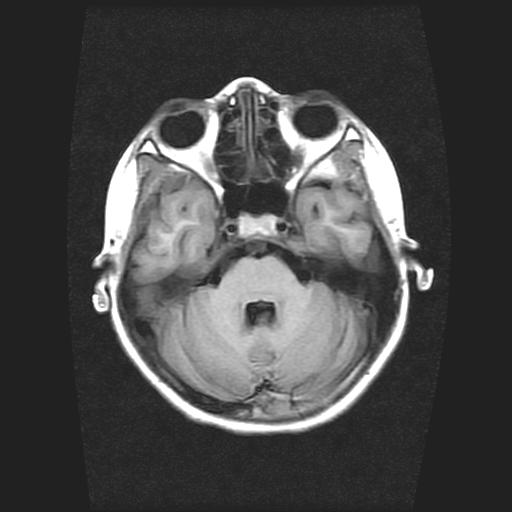

9岁女孩,三岁时诊断为癫痫,一直服丙戊酸钠,现患者一般情况良好,家长复查核磁片,看能否停药..

巨脑回